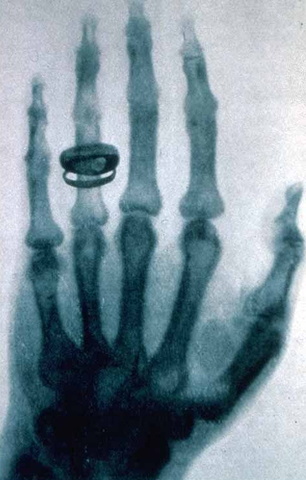

• Rayos X

Rayos X

El físico alemán Wilhelm Röntgen, descubre los rayos x mientras trabajaba con un tubo de rayos catódicos.